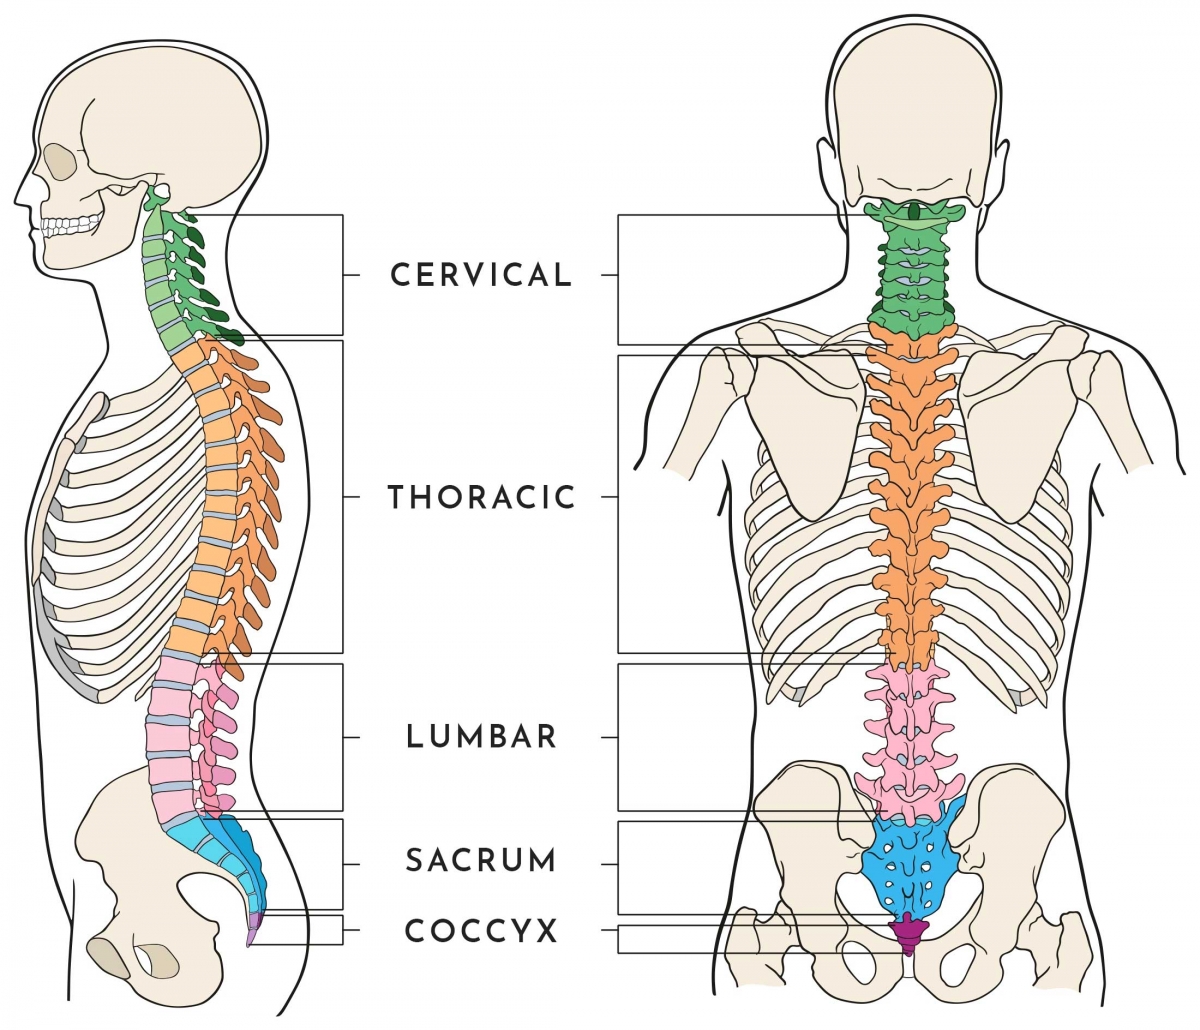

silikonsheet.blogg.se – Spine diagram

Anatomy of the Spine | Globus Medical

Anatomy of the Spine | Wessex Spinal Surgeon

Spine Anatomy and Back Pain – The Core Expert

human spine anatomy diagram